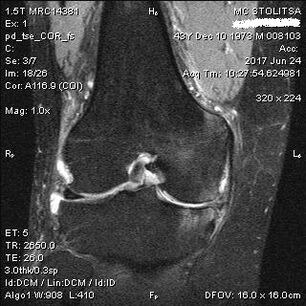

The diagnosis of osteoarthritis of the knee joint is made in the office of a rheumatologist or orthopedist.The doctor examines the affected joint, palpates it, listens to complaints and asks additional questions.Perform various tests, for example, asking the patient to bend their leg or walk a few steps.Then, if it is necessary to clarify the stage of the disease or the nature of pathological changes, he will refer you to additional studies.For example, for CT scan or x-ray.